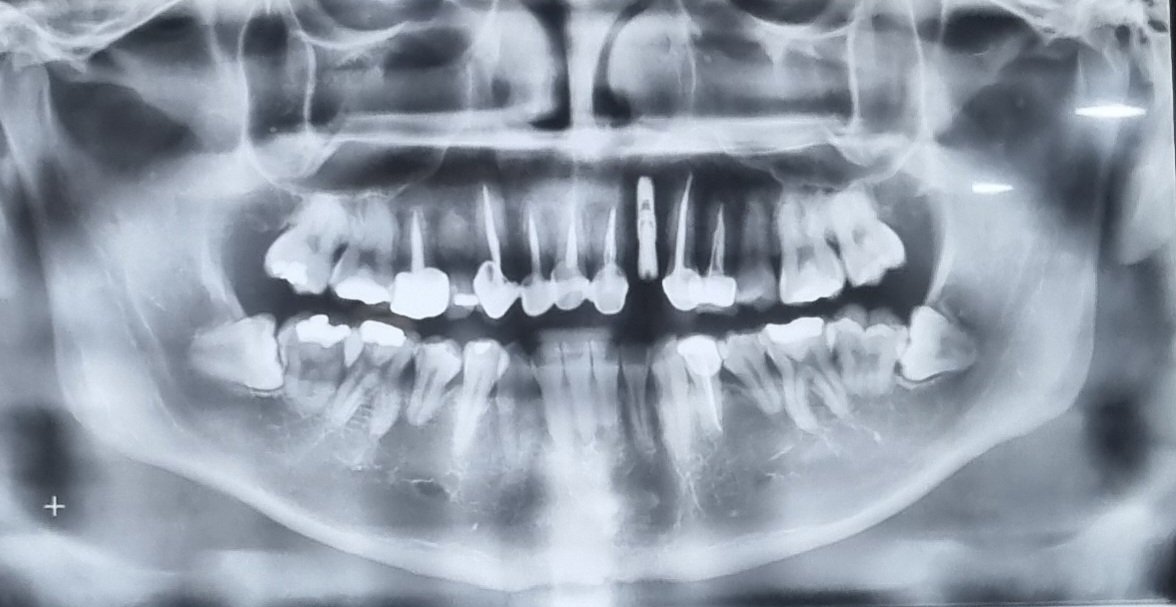

치아관리 꼭 열심히하셈...

아직 대학생인데 크라운 8개 임플란트 하나있음.....

어릴때 부모님이 관리 안해줘서 초,중딩때부터 신경치료함.

성인되고 치아상태보니 미래가 ㅈㄴ 막막해서 부모님 원망스럽다....